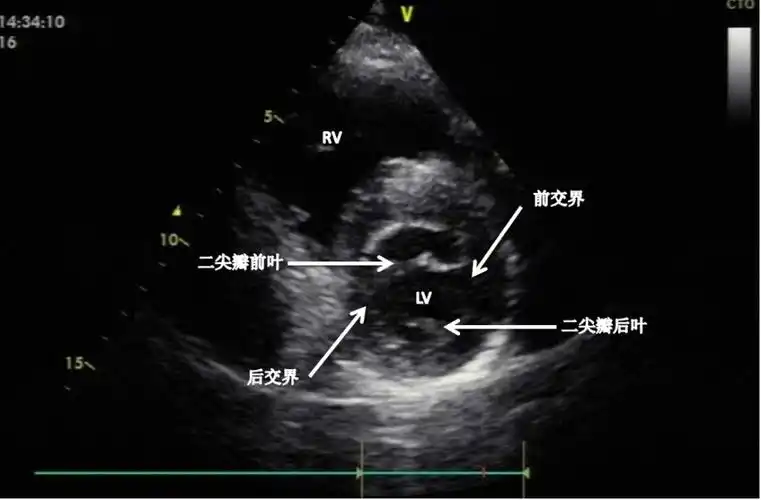

胸骨旁左心室短轴切面上魏相东读图谈心零基础入门心脏超声